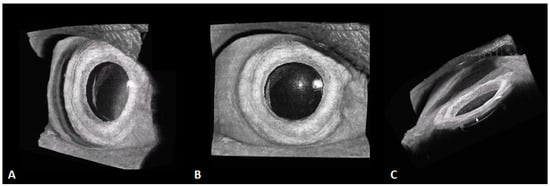

Figure 10.

These 3D, 400-kHz SS-OCT images demonstrate an eye with an intraocular lens (IOL) with a small pterygium on the nasal side. (A) The structural relationship between the IOL and the iris is clear. (B) The frontal view. (C) The side view, in which the entire side of the iris is clearly visible (white arrow), as well as the lower interface of the IOL.